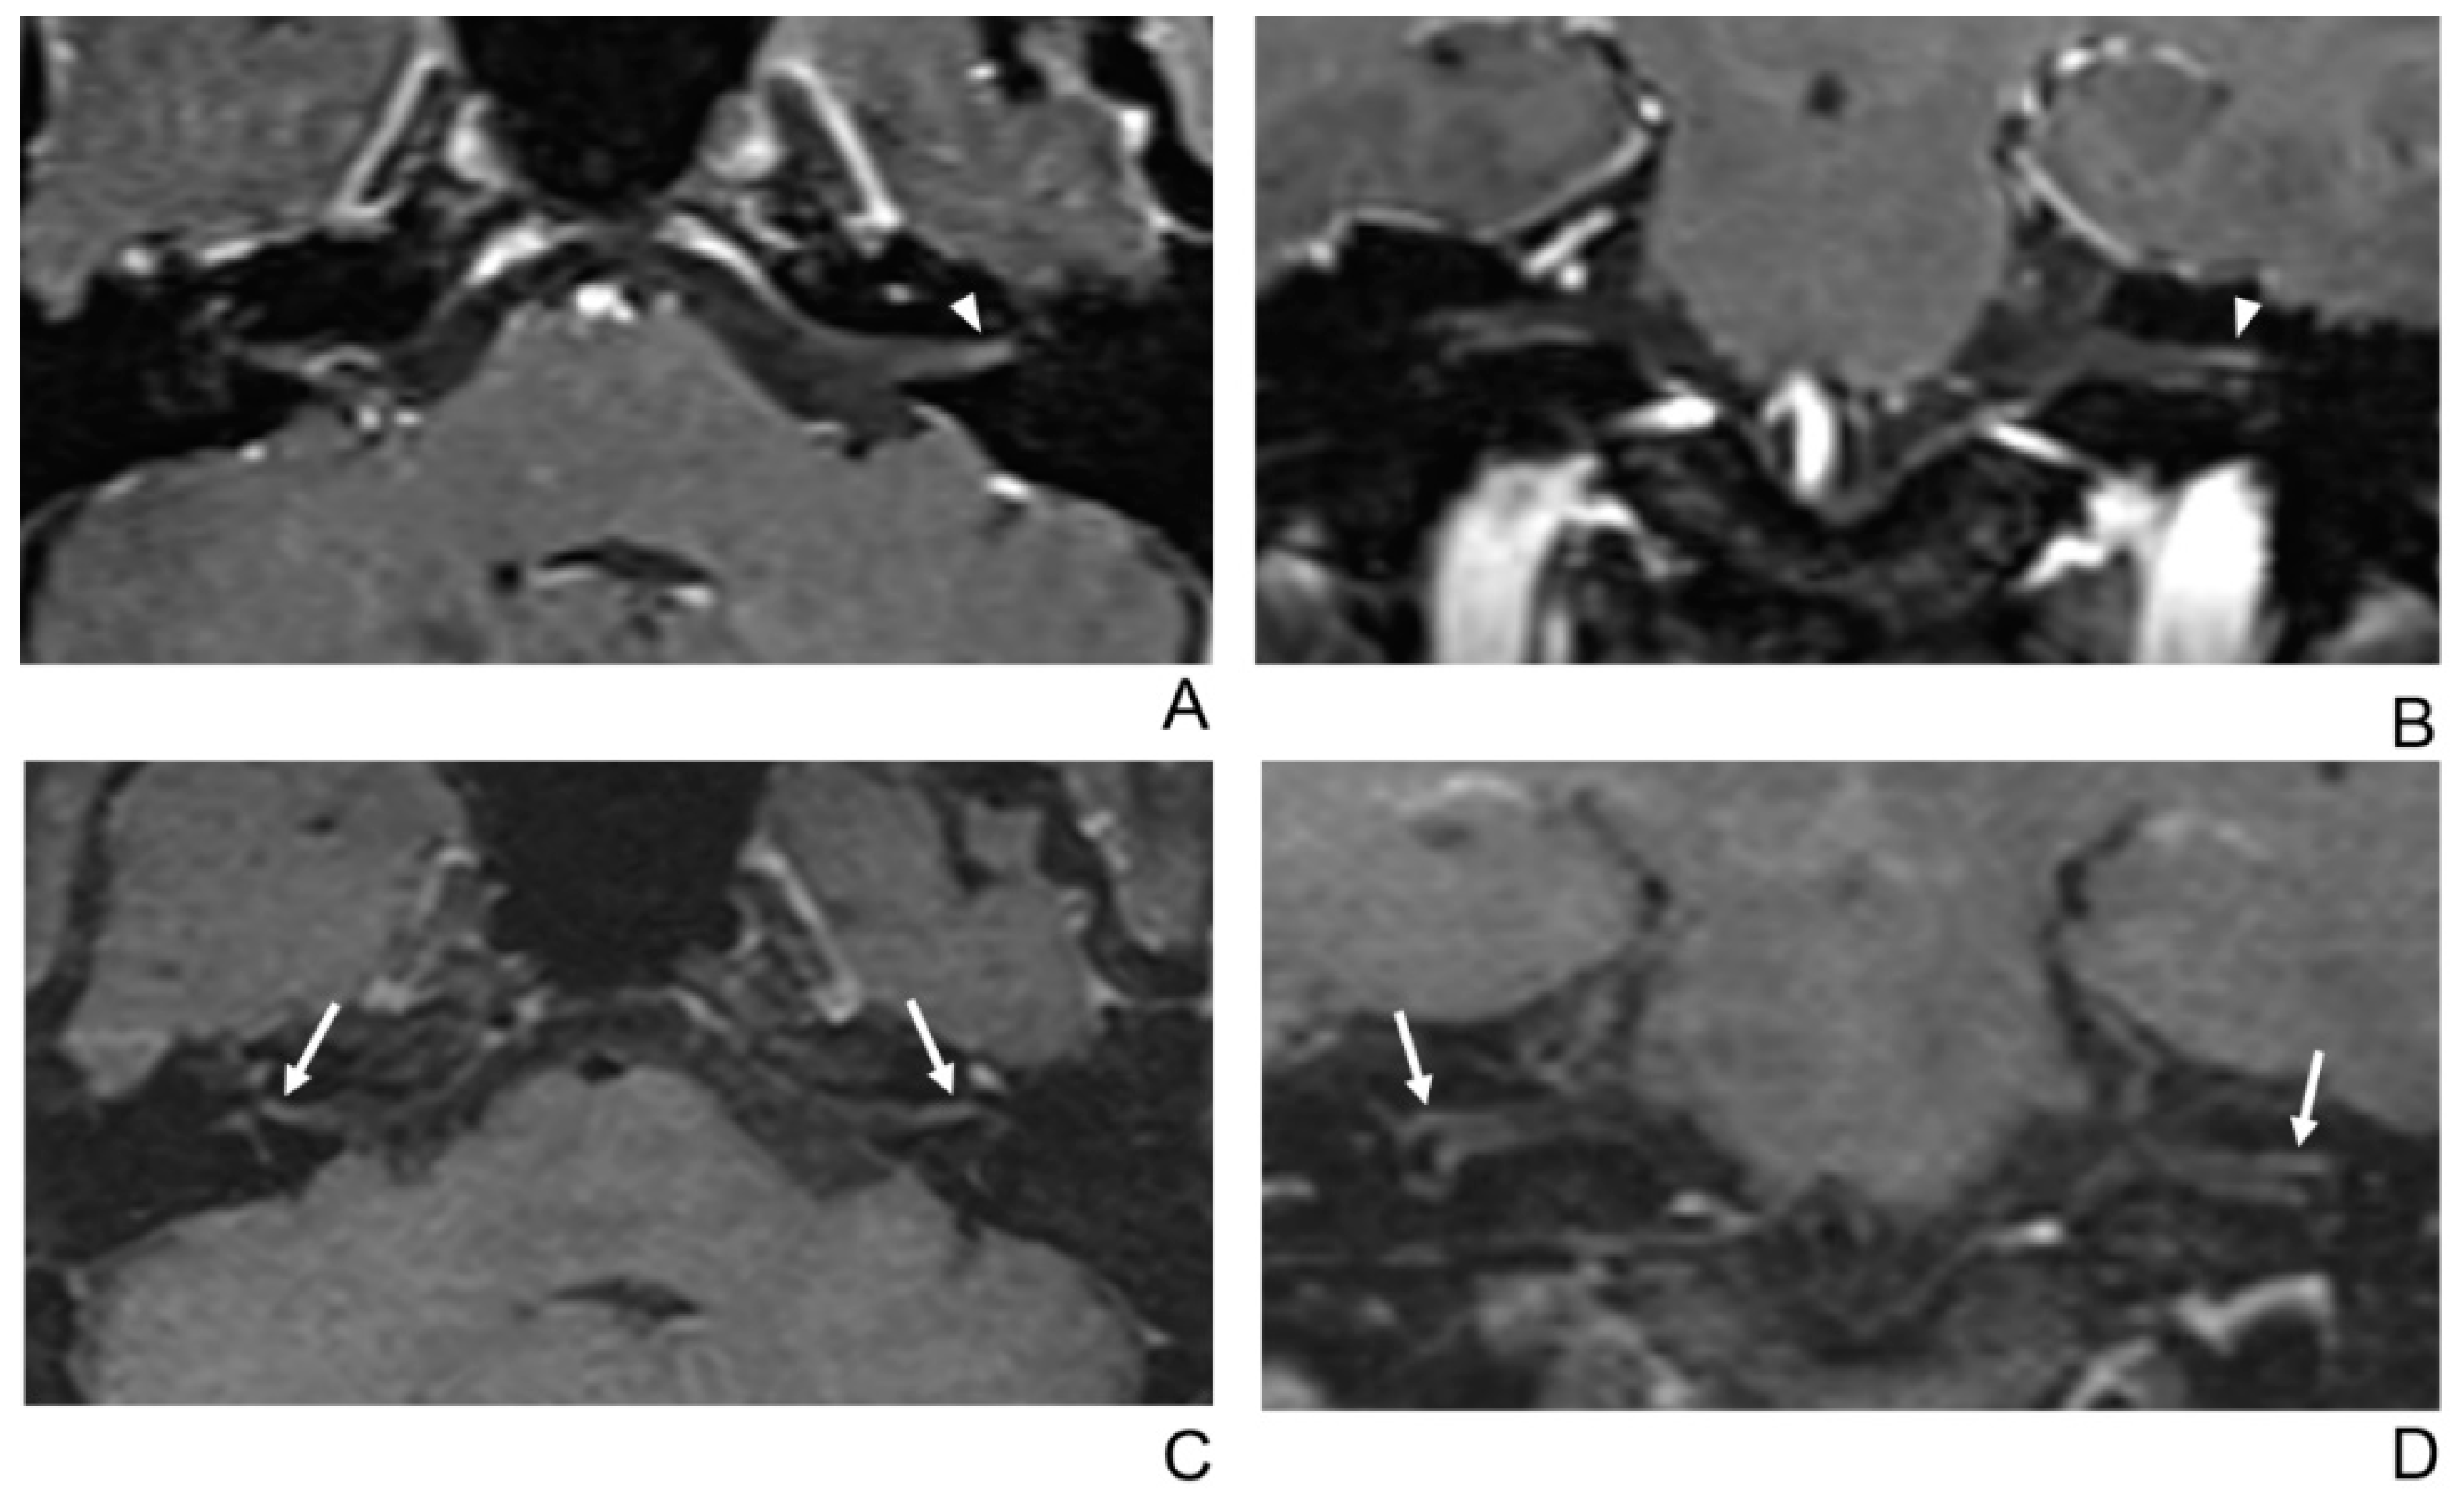

Figure 4.

A 56-year-old female patient with right facial neuritis. (A–D) Paired axial and coronal CE-GRE (A,B) and T1 BB-FSE (C,D) images of the same patient. In the axial (A) and coronal (B) CE-GRE images, no definite asymmetric enhancement was demonstrated in the bilateral facial nerves (arrowheads); thus, it was evaluated by reviewers 1 and 2 as normal facial nerves (false negative). In contrast, the right facial nerve shows asymmetric intense enhancement in the canalicular, labyrinthine, and anterior genu segments in the T1 BB-FSE axial (C) and coronal (D) images (arrows); thus, the two reviewers interpreted the enhancement as right facial neuritis (true positive; 2, diagnostic confidence; 3, 2, and 3, visual grades for CE in the canalicular, labyrinthine, and anterior genu segments, respectively).